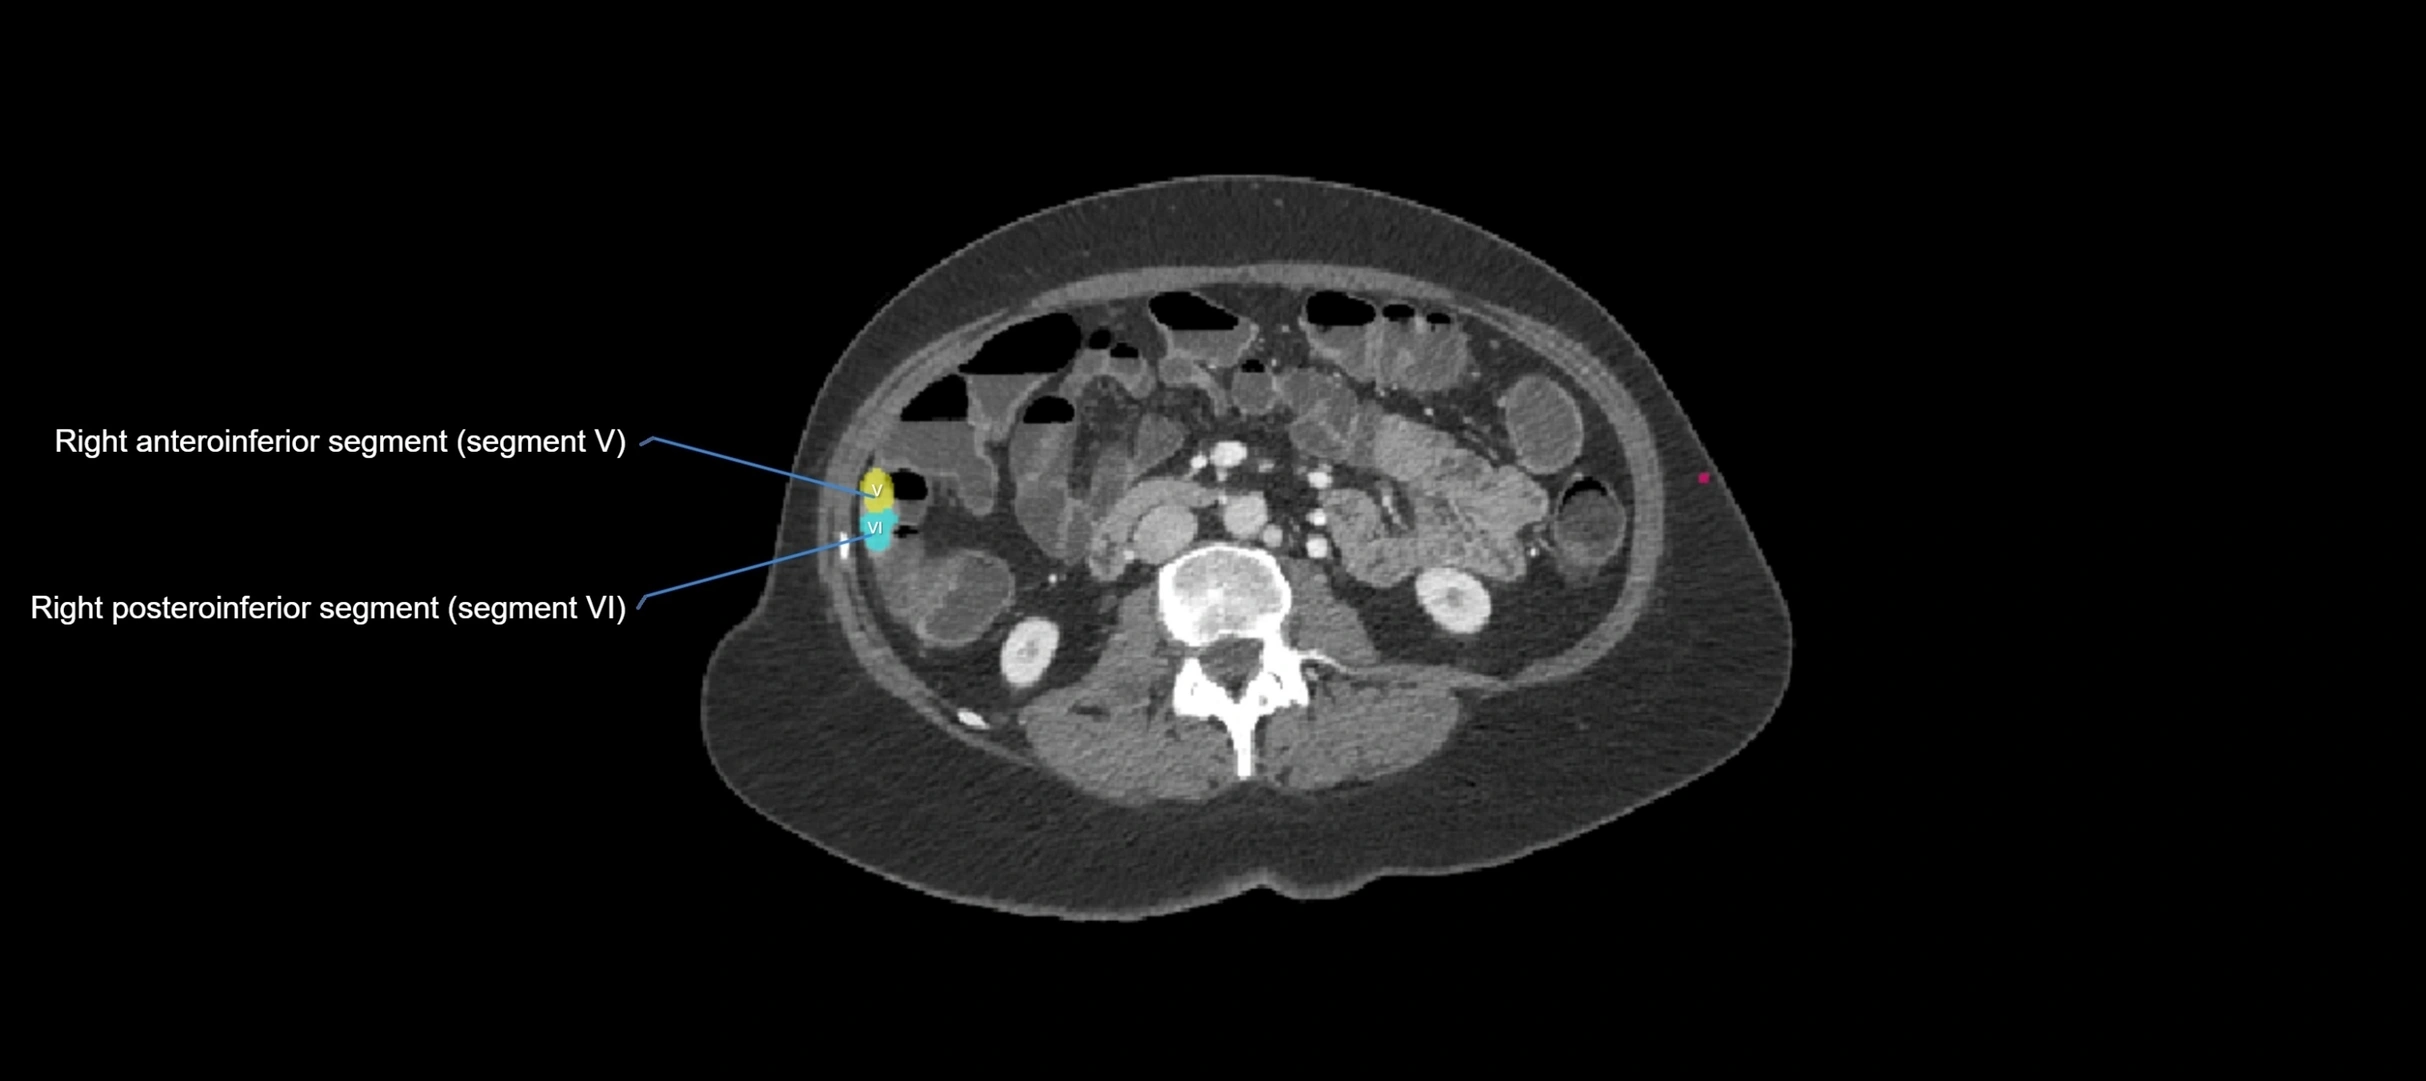

MRI image

image